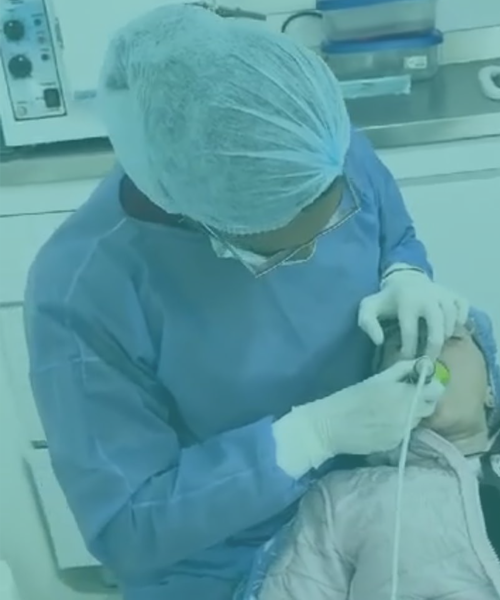

Soy odontólogo especialista en Periodoncia y Oseointegración, con una trayectoria dedicada al diagnóstico, prevención y tratamiento de enfermedades de las encías, así como a la colocación de implantes dentales con técnicas avanzadas y mínima invasión.

Su enfoque combina ciencia, precisión y empatía, priorizando siempre la salud integral del paciente y la estética natural de la sonrisa. Cada tratamiento es diseñado de manera personalizada, utilizando tecnología de vanguardia, materiales biocompatibles y protocolos clínicos seguros.

El Dr. Juan Camilo Arias utiliza técnicas avanzadas de raspado, alisado radicular y regeneración tisular guiada para detener la pérdida ósea y mantener tus dientes firmes y saludables.

Con técnicas de oseointegración avanzada, el Dr. Arias planifica cada caso con precisión digital para lograr una sonrisa natural, firme y segura.